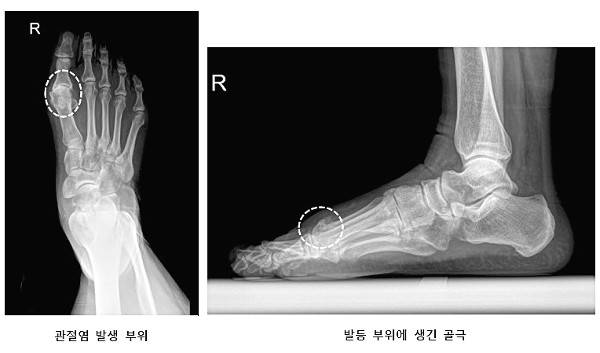

엄지 발가락에 관절염이 생기면 발가락이 위로 잘 안 움직여지고 발등 쪽으로 들어올리려 할 때 통증이 나타난다. 무지 강직증은 특이하게 연골 손상과 함께 관절을 이루는 ‘중족골’의 발등 부위에 뼈가 가시처럼 자라나는 골극이 발생한다. 이 때문에 엄지 발가락을 위로 들어올리거나 뒤꿈치를 드는 동작에서 발가락 뼈와 골극이 부딪히면서 관절 움직임이 감소하고 통증을 일으킨다. 발가락 관절 부위에 뼈가 자라기 때문에 겉으로 볼 때 튀어나와 보이고 걷기나 운동 등 일상생활 중 통증과 부기가 있을 수 있다. 맨발로 걷거나 뒷굽 높은 신발을 신을 때 통증이 악화된다.